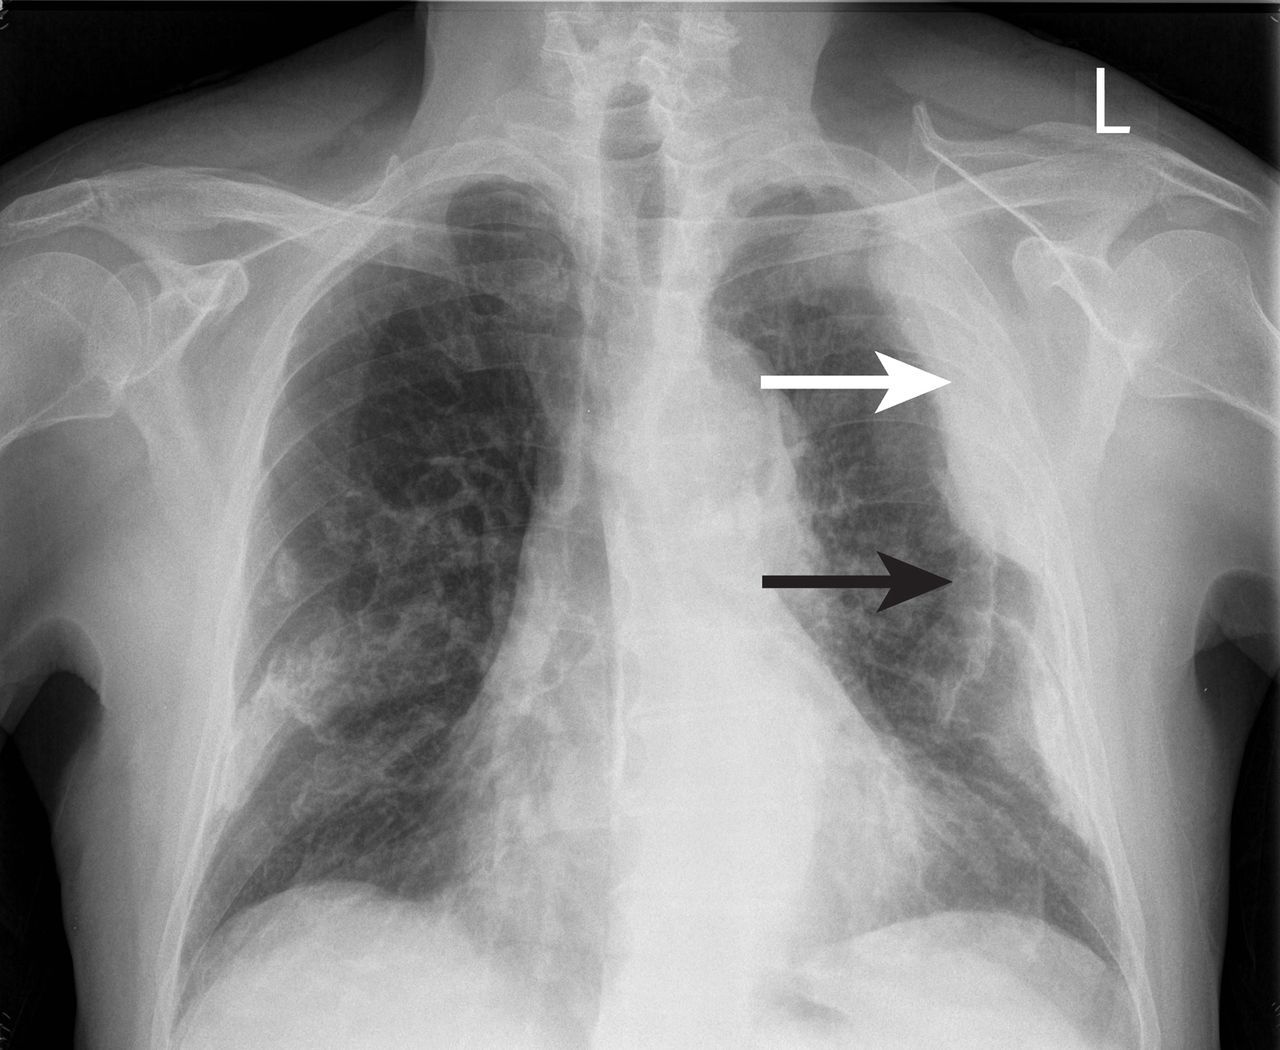

What does loss of definition of right heart border indicate?

Right middle lobe consolidation

What does loss of the aorto-pulmonary window suggest?

Mediastinal lymphadenopathy = malignancy